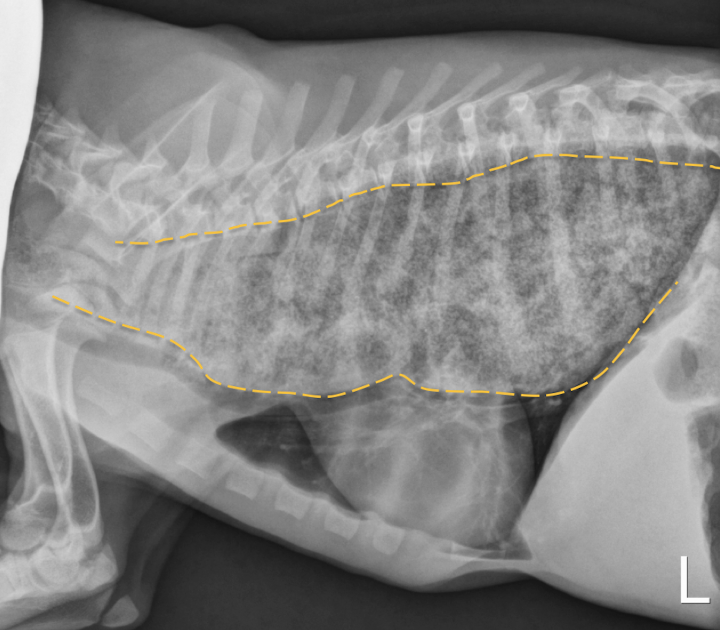

A

Juvenile idiopathic megaesophagus